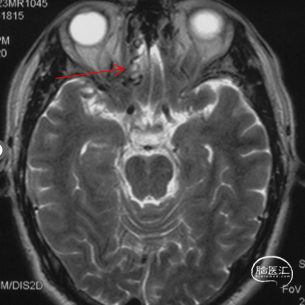

1年前头颅MRI:

DWI可见右侧基底节区新发脑梗,T2 上见额底异常血管流空影。

MRA见额底部异常扩张的血管。